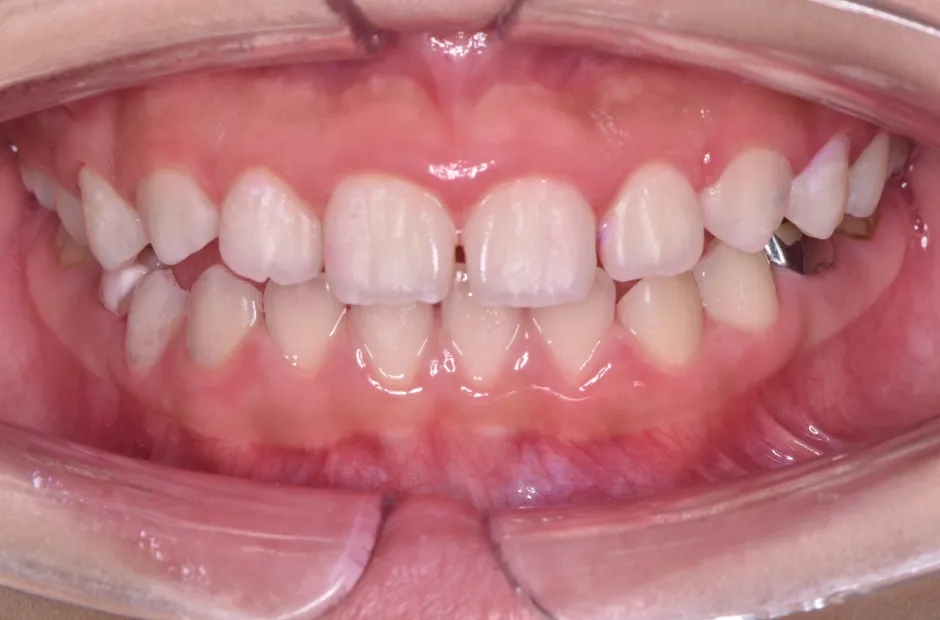

拡大床装置

叢生

| 診断名・主訴 | 叢生 |

|---|---|

| 年齢・性別 | 10歳・女性 |

| 治療期間・回数 | 2年半 |

| 治療に用いた主な装置 | 拡大床装置 |

| 抜歯部位 | なし |

| 治療費 | 30万円(税抜) |

| リスク・副作用 | 装置による違和感・疼痛・歯肉退縮・歯根吸収・虫歯のリスクなど |

治療前

治療中

治療後